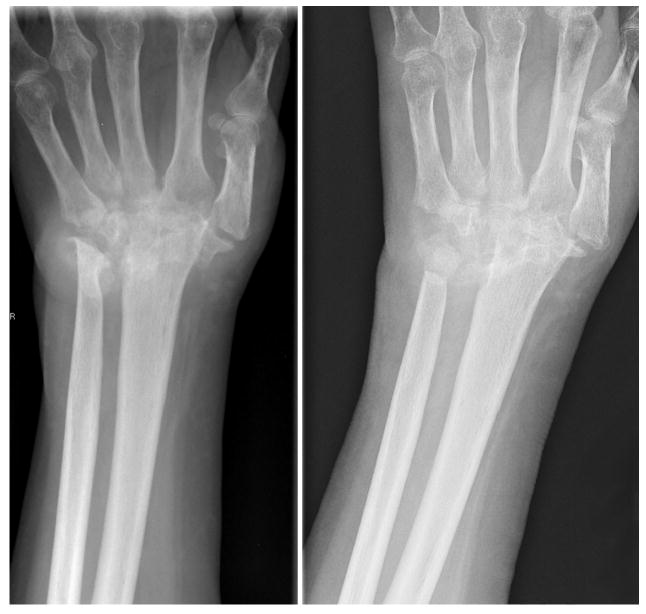

Three view radiographs of the hands and wrists are mandatory to evaluate radiographic changes in the joints. The amount of articular or bony destruction seen on radiograph does not necessarily correlate with patients' complaints. Often, patients with minimal wrist pain have advanced wrist collapse on radiographs. Preoperative evaluation of the neck and cervical spine is essential because a substantial proportion of RA patients have atlanto-axial subluxation. Instability of the cervical spine should be evaluated prior to having surgical procedures. Ideally, regional anesthesia is preferred, but some patients may require general anesthesia.

The wrist is the earliest and most frequent site of RA hand disease. Destruction of the ulnar carpal ligamentous structures leads to a syndrome called “caput ulna syndrome.” This “ulnar head syndrome” is marked by dorsal subluxation of the distal ulna. The inflammation of the dorsal soft tissue envelope leads to weakening of the dorsal supporting structures. Supination of the carpus subsequently occurs due to loss of dorsal support and the volar displacing force of the flexor tendons. This volarly displacing force is exacerbated by volar subluxation of the ECU. Inflammation of the radial sided structures further deforms the wrist. Unopposed pull of the radial wrist extensors leads to radial deviation of the metacarpals and a resultant ulnar deviation of the phalanges. In addition, the loss of dorsal soft tissue support leads to dorsal dislocation of the ulnar head and weakening of the distal radial-ulnar joint (DRUJ). In advanced disease, there is complete collapse of the wrist with volar dislocation of the carpus and dissociation of the DRUJ. Radiographs are often worse than the clinical picture. Treatment is targeted at patient concerns and not radiographic findings. Operative interventions for the RA wrist are mainly reconstructive. Total synovectomy is impossible because access to the many recesses in the wrist joint is quite difficult and partial synovectomy alone provides limited long-term benefit.

Radiocarpal articular wear requires arthroplasty or arthrodesis (Fig 5). Both procedures are indicated for deformity and instability that interfere with function or cause persistent pain. Prerequisite requirements for arthroplasty include good pre-operative wrist motion, functional wrist tendons, and good bone stock. In addition, adequate soft tissue is necessary to stabilize the wrist implant. Wrist arthrodesis is a predictable procedure and has a low complication rate. It is contraindicated in patients with severe shoulder and elbow diseases because patients may not be able to adapt to loss of motion in all three joints. Compared to arthrodesis, the post-operative rehabilitation program for arthoplasty is generally more difficult and is associated with higher risk of complications. The wrist mobility with arthroplasty is traded for the predictability with arthrodesis. Older methods of arthroplasty included the use of silicone or metal/polyethylene implants. An expanding number of total wrist replacement systems are increasing reconstructive options (6). Complications of wrist arthroplasty include fracture, infection, implant failure, implant dislocation, and implant loosening. For patients with bilateral wrist problem, arthrodesis is recommended in the dominant hand to maintain stability for gripping and power. The non-dominant hand is treated with arthroplasty to maintain some joint motion needed for self-hygiene. Destruction of the radiocarpal joint with preservation of the midcarpal joint may be treated with limited arthrodesis, which maintains about 25-50% of wrist motion through motion at the midcarpal joint.

Fig 5.

Surgical treatment options of the rheumatoid wrist includes arthodesis using Steinmann pins (left) or plating (center). Alternatively, prosthetic total wrist arthroplasty (right) can be performed.